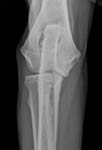

Gesundheitsstatus vom 26.11.2018 Die Röntgenbilder zeigen keinen Hinweis auf HD oder ED bei Lena vom Gehrensee. Die veterinärmedizinischen Untersuchungen von Jana auf HD, ED u. DCM und die Zuchtzulassungsprüfung wurden erfolgreich bestanden.

Die Gelenke sind HD und ED - frei, das Herz ohne Befund. Vor dem Hintergrund, dass seit 5 Generationen alle Zuchthündinnen bis ins hohe